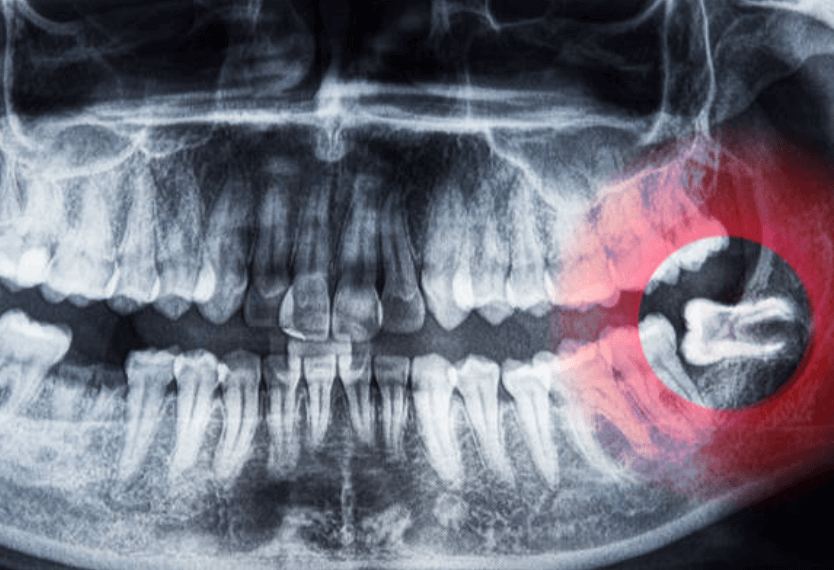

사랑니를 뽑으면 구멍이 생기는 것은 단순발치, 단순매복, 복잡 매복, 완전매복 등 케이스와 상관없이 무조건 생깁니다. 이빨을 뽑은 후에는 피가 채워지고 혈액 응고 작용으로 피가 굳어지는 과정을 거칩니다.

드라이 소켓(Dry socket)은 응고된 피가 떨어지거나 완전히 아물지 않아 발생하는 상황입니다. 드라이 소켓이 생기는 원인은 아직 밝혀지지 않았지만, 일부 환자들은 노력해도 해결되지 않을 수 있습니다.